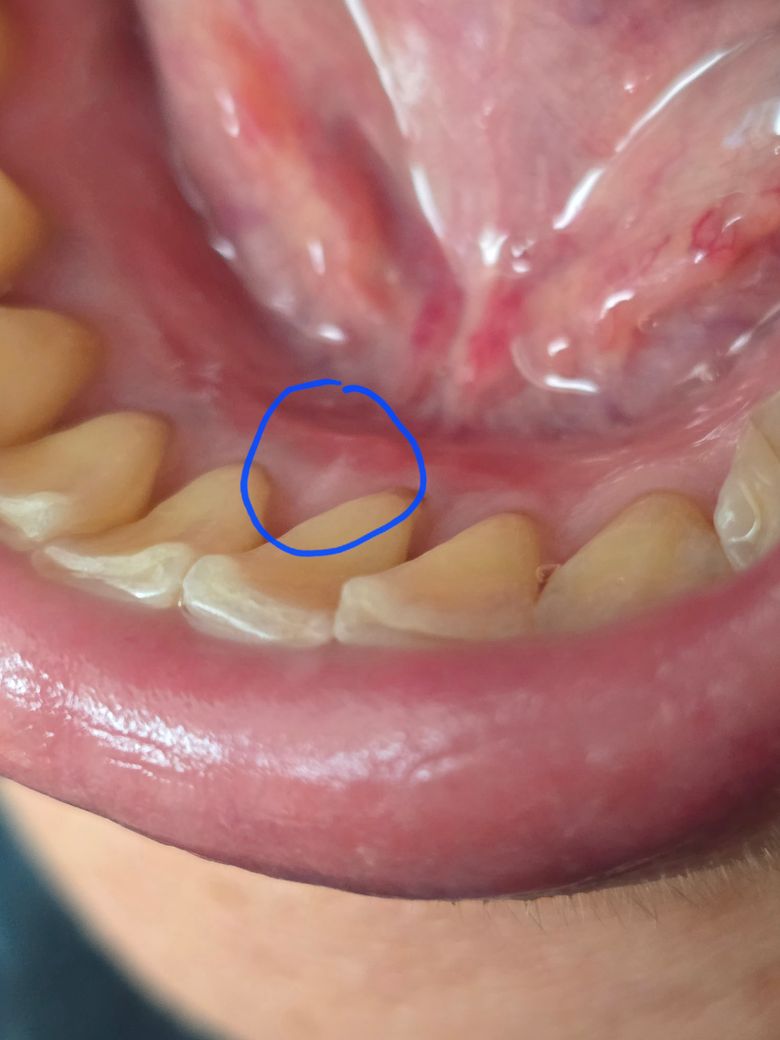

잇몸에 흰반점이 있는데 무엇인지 궁금합니다

발병당일과 9일후 사진

잇몸에 구내염이 생겨 관찰하다

흰반점이 있는걸 보았습니다

그다음날 조금 줄어들더니

일주일후 지금 잔흔이 조금 남아있습니다 무엇인가요?

마찬가지로 구내염으로 인한 상처와 흉터로 보압니다. 상처가 아물면서 하얀 주름을 보일 수 있으며 대부분 시간이 지나면서 사라지게 될 것으로 보입니다